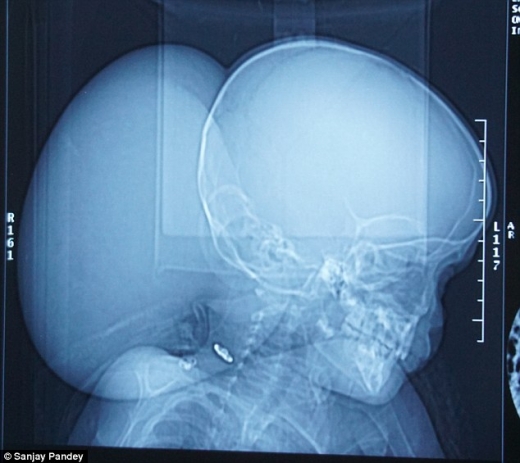

레누는 최근까지 후두부에 무게만 2.5kg에 달하는 거대 종양이 있었다. 모친 프라밀라의 말로는 태어났을 때는 아무 이상이 없었지만 어느 날 갑자기 머리에 무언가 덩어리 같은 게 생겨났다는 것.

레누의 종양은 ‘거대 후두 뇌류’(giant occipital encephalocele). 이는 시력에 영향을 줄 수 있는데 세계에서 두 번의 사례 밖에 보고되지 않았다고 수술을 집도한 S.N. 쿠릴 박사는 말했다.

쿠릴 박사는 “눈에 시야를 공급하는 필수 시신경에 손상 없이 종양을 제거하는 것이 주 과제였다”면서 “수술 동안 손상이 생겼다면 이후 아이는 영구적으로 시각을 잃었을 것”이라고 말했다.